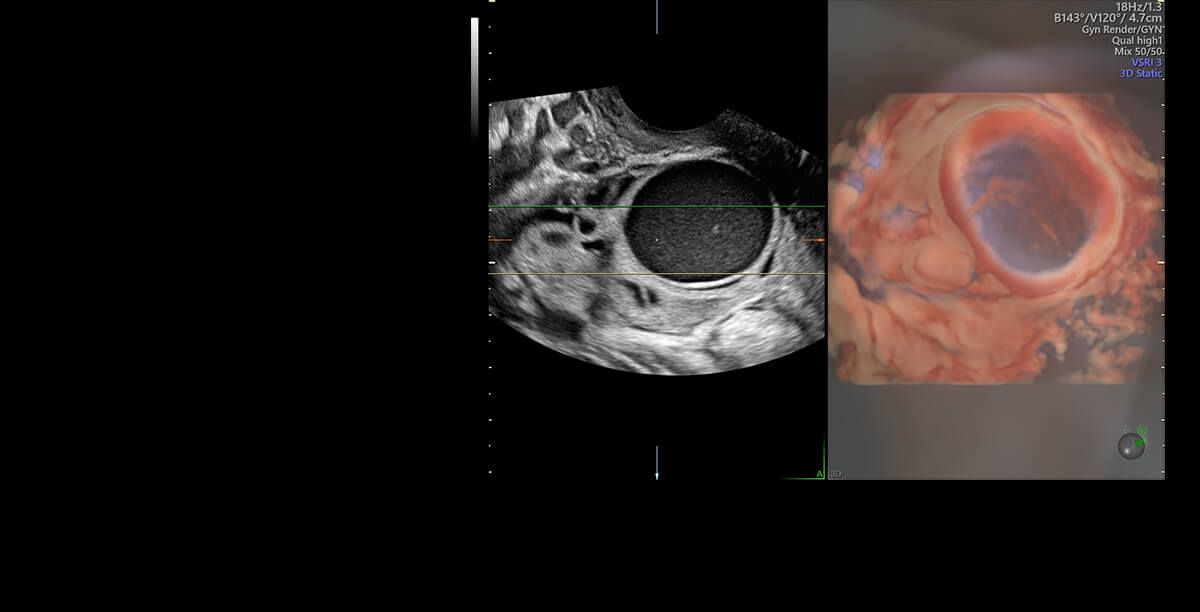

Jestem lekarzem, ginekologiem-położnikiem, absolwentką Collegium Medicum Uniwersytetu Jagiellońskiego w Krakowie. Przez długi czas byłam związana z Katedrą Ginekologii i Położnictwa Uniwersytetu Jagiellońskiego Collegium Medicum w Krakowie jako nauczyciel akademicki. W 2007 roku uzyskałam nostryfikację dyplomu lekarskiego w Stanach Zjednoczonych. Tytuł doktora nauk medycznych uzyskałam na podstawie obronionej rozprawy doktorskiej z zakresu problematyki układu immunologicznego w ciąży pozamacicznej. Praca lekarza jest moją wielką pasją, a moje doświadczenie kliniczne zdobyłam pracując w Oddziale Ginekologii i Onkologii Szpitala Uniwersyteckiego w Krakowie. Jestem doświadczonym specjalistą w zakresie ultrasonografii położniczej, ginekologicznej i onkoginekologicznej, a wszystkie badania wykonuję zgodnie z najnowszymi rekomendacjami Sekcji Ultrasonografii Polskiego Towarzystwa Ginekologicznego, Fetal Medicine Foundation (FMF) oraz The International Society of Ultrasound in Obstetrics and Gynecology (ISUOG). Moje zainteresowania dotyczą również zagadnień dotyczących diagnostyki i leczenia niepłodności oraz metod wspomaganego rozrodu. W trosce o najlepszą opiekę nad Pacjentkami staram się poszerzać moją wiedzę przez uczestnictwo w licznych kursach i kongresach. Będąc lekarzem, a zarazem kobietą mam świadomość jak intymnym przeżyciem jest wizyta u ginekologa, dlatego zwracam uwagę na indywidualne podejście do każdej Pacjentki, tak jak sama chciałabym być leczona będąc Pacjentką.

I am a physician, a gynecologist- obstetrician. I graduated from the Jagiellonian University Medical College. For a long time, I worked as a university teacher at the Department of Gynecology and Obstetrics, Jagiellonian University Medical College. In 2007, my medical doctor’s diploma, which I received in the USA, was officially recognized. My MD-PhD I obtained on the basis of my doctor thesis dealing with the problems concerning the immune system in the ectopic pregnancy. This profession is my passion. I gained my experience working at the Department of Gynecology and Oncology in the Krakow University Hospital. I am an experienced specialist in obstetric, gynecologic and oncologic ultrasound, and all of my examinations are carried out according to the newest recommendations of the Ultrasound Section of the Polish Gynecological Society, Fetal Medicine Foundation (FMF) as well as The International Society of Ultrasound in Obstetrics and Gynecology (ISUOG). My interests also include issues concerning the diagnosis and treatment of infertility and methods of assisted reproduction. Out of concern for my Patients, I constantly try to extend my knowledge through participating in numerous courses and congresses. Being both a doctor and a woman, I am aware of the intimacy of an appointment at a gynecologist, and that is the reason why I pay a special attention to an individual approach to each of my Patients, which is the way I would like to be treated as a Patient. Best regards, Anna Knafel

Badania drożności jajowodów